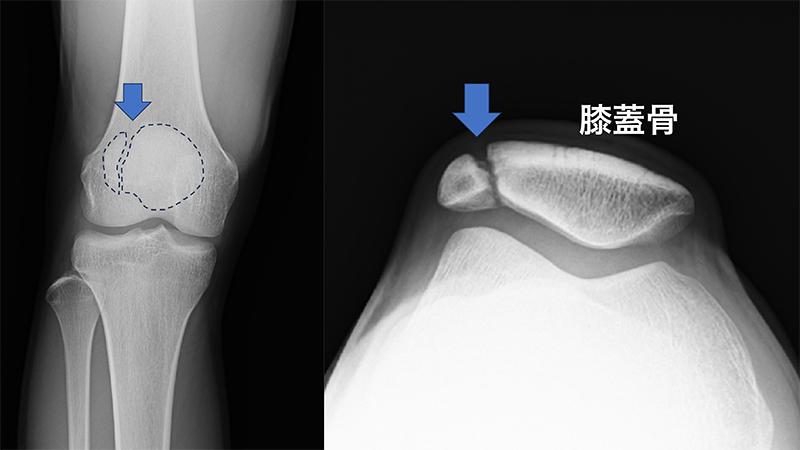

1.分裂膝蓋骨(二分膝蓋骨)

膝蓋骨は、太ももの大腿四頭筋という大きな筋肉の腱の中にあり、筋肉を効率よく働かせたり、腱の摩耗を減らしたり、関節を安定させたりと膝の重要な役割を担っています。一般的に「お皿の骨」と呼ばれ、2歳くらいから徐々に骨化がはじまります。膝蓋骨は一つの骨化中心から形成されますが、2割くらいのこどもには複数の骨化中心が存在していて、通常は複数の骨化中心が癒合して1つの膝蓋骨になるのですが、数%では癒合がおこらず、それぞれが独立した骨として成長し複数に分かれた膝蓋骨になることがあります。単純レントゲンやCT検査では、膝蓋骨が複数に分かれていて、境界部分がその名のとおり「分裂した」膝蓋骨となって確認されます。無症状であれば問題はありませんが、ジャンプやダッシュなどの繰り返し動作によって分裂部にストレスが生じると炎症が起こり、膝の痛みの原因となります。分裂膝蓋骨の発生形態によって3つのタイプに分かれますが、特に膝蓋骨の上外方にあるタイプは痛みが生じやすく、治療が必要になることがあります。